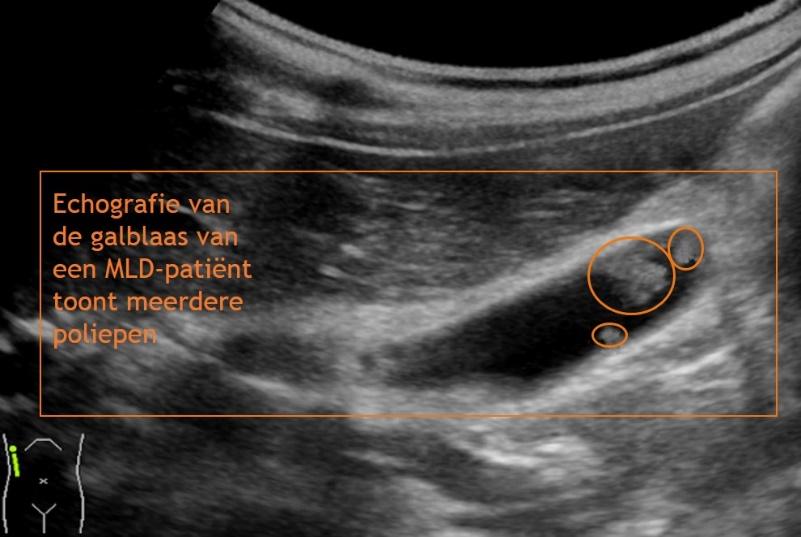

Echografie van de galblaas